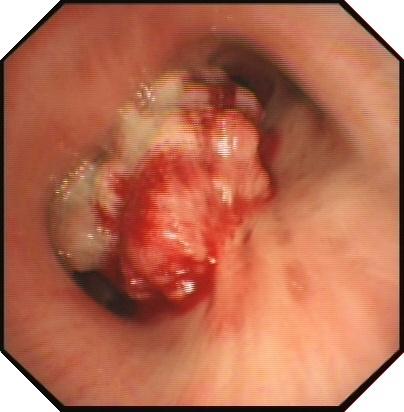

病例1:结核所致右主支气管瘢痕性狭窄

病例2 恶性肿瘤所致气管狭窄

理结果:鳞癌.